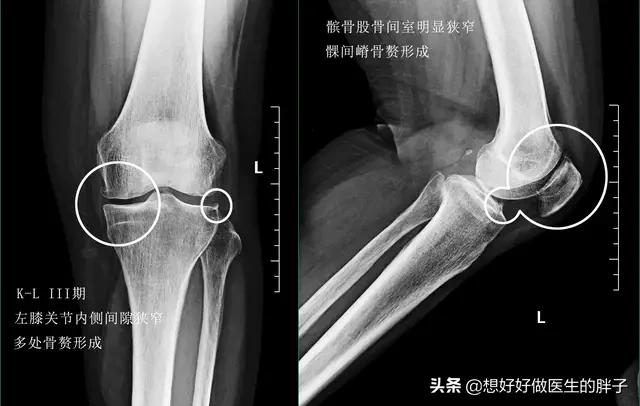

到了关节软骨磨损的晚期,很可能关节内负重区的软骨已经被磨得消失殆尽了。所以患者的关节往往会出现明显的间隙狭窄和大量的骨赘形成,此时的患者,严重的关节屈伸角度也会有明显的受限,而且疼痛会对患者的整个生活造成非常大的困扰,有些比较重的患者甚至会出现休息的时候关节也疼痛,而且在夜间休息的时候能疼醒,此时以前的一些治疗方法就很难帮助患者解决问题了,进行关节置换或者是部分关节置换,是解决患者问题的最佳措施(康复锻炼一样要做)。